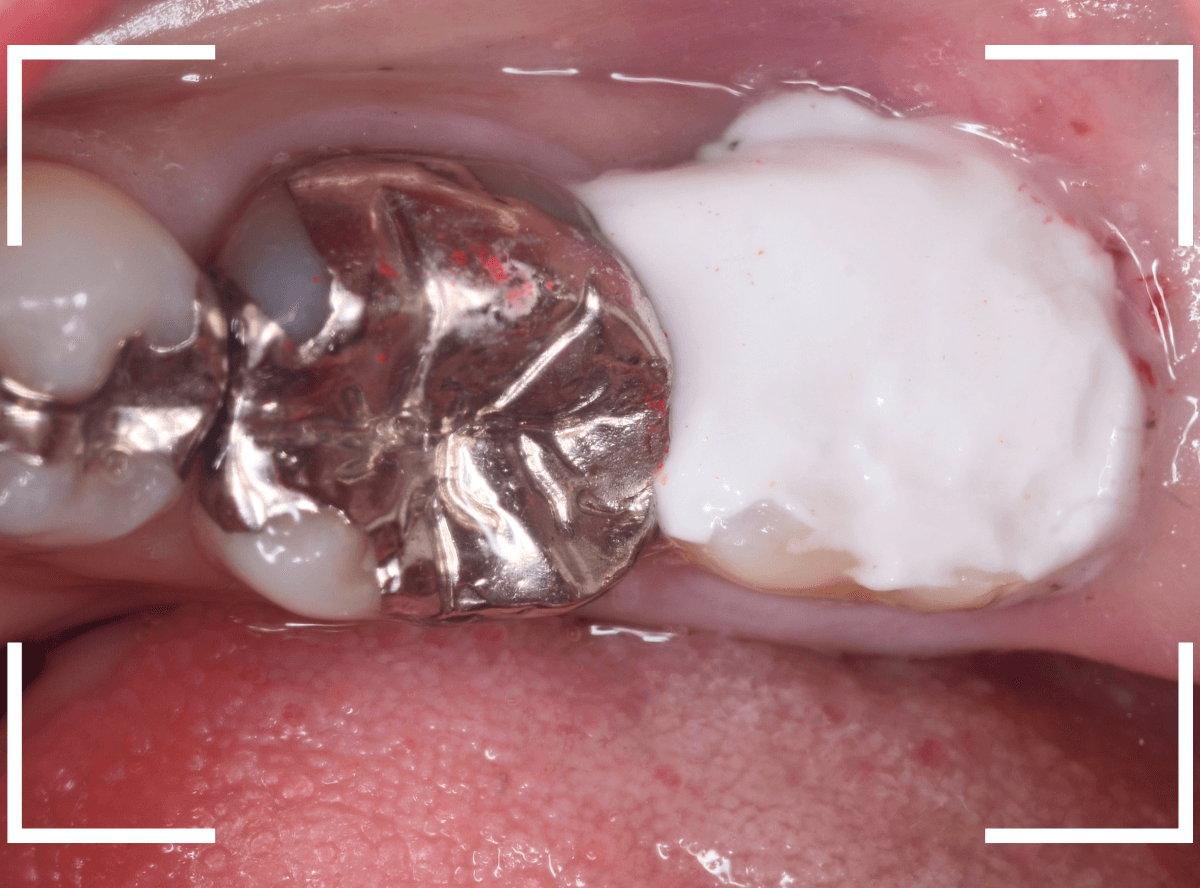

中のお薬も慎重に外して虫歯を除去します。

虫歯が深く、歯肉の下まで浸食していましたので、歯肉を部分切除し、虫歯を全て除去したところで、奇跡的に神経スレスレの状態でとどまっていました。

何とも言えませんが、神経を残せる可能性が出てきました。

虫歯が神経まで達していなくても、治療前から自発痛(何もしなくても痛い)があれば、神経をとらなければいけません。

今回は、そこまでの症状がありませんでしたので、患者さんと相談の上、神経を取らずに残す方法で様子を見る事になりました。

痛みが出ませんように。。。